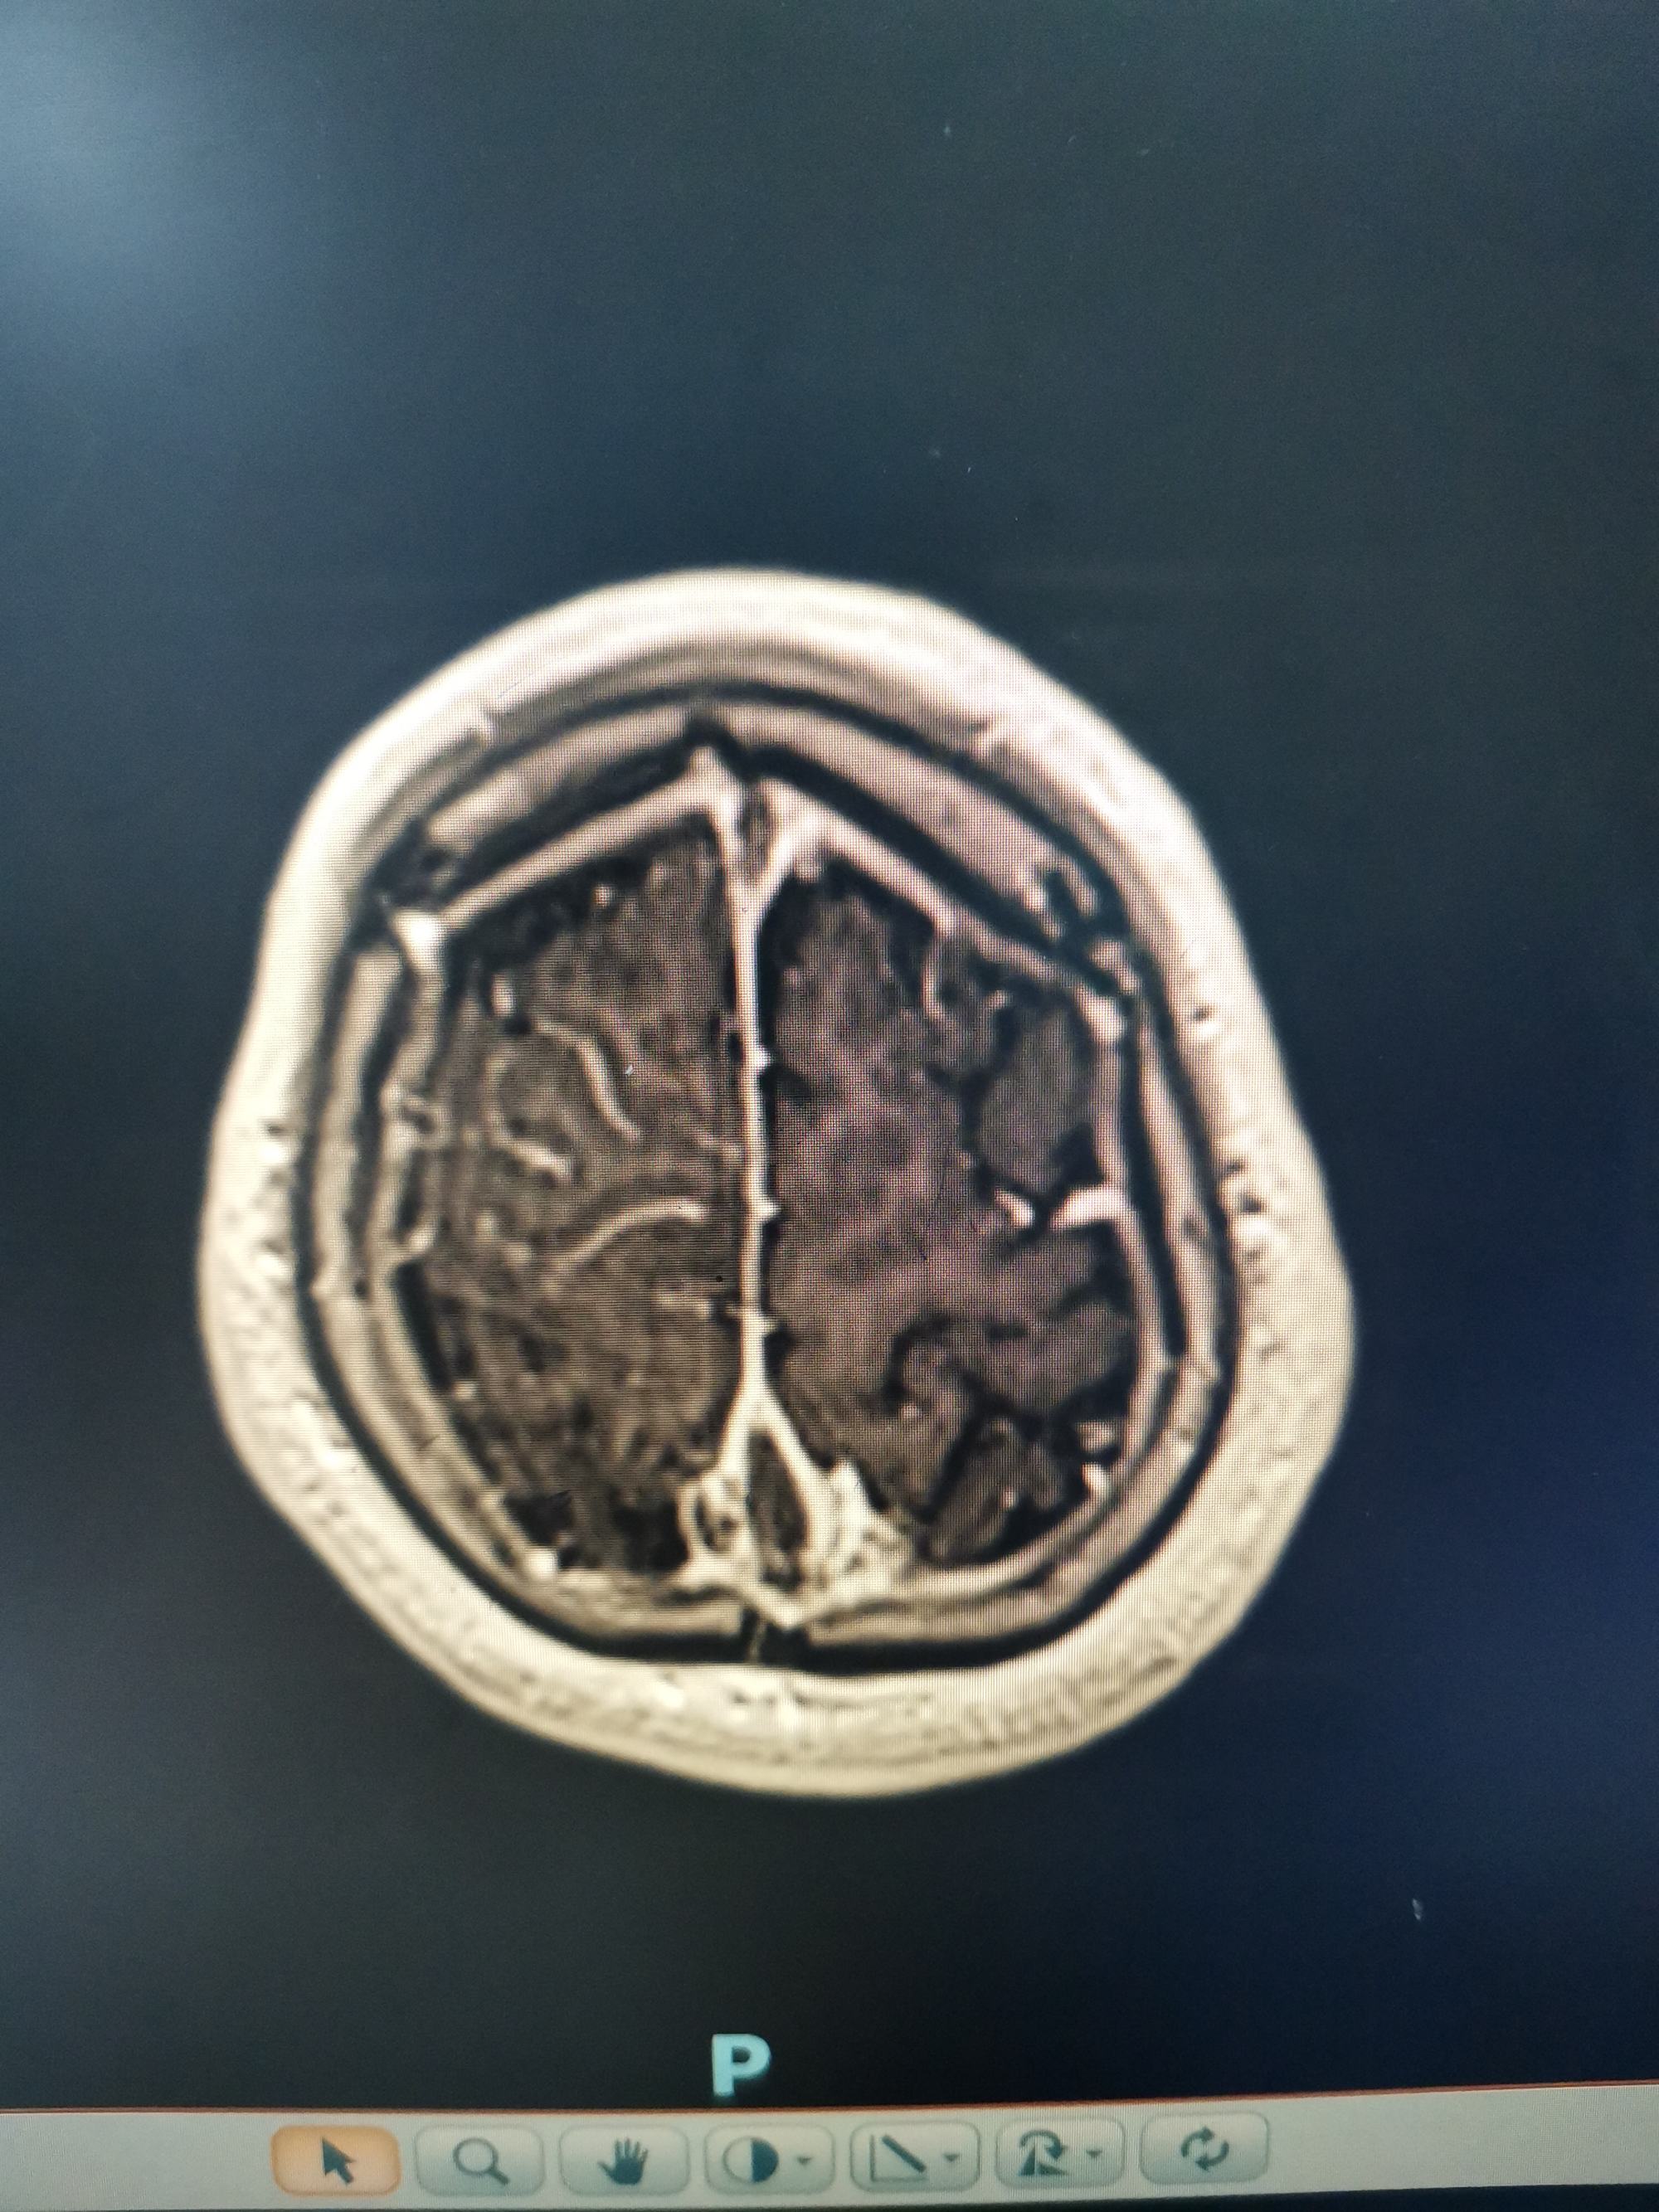

增强显示矢状窦长节段充盈缺损,D-2聚体大于正常上限5倍以上。我科诊断考虑上矢状窦血栓形成伴多发多次脑梗死伴出血。

矢状窦全程血栓,与外院相比血栓明显扩大。立即急诊行脑血管造影+介入取栓术。

矢状窦是大脑最大的回流静脉,相当于颅内的长江,长江主干闭塞,各支流必将洪水泛滥。患者随时可能再发脑梗和脑出血可能。立即急诊行脑血管造影+介入取栓术。